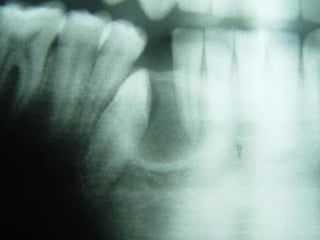

Granuloma (Lesão) Periférico de Células Gigantes A excisão cirúrgica deve ser antecedida de exame radiográfico, pois lesão não completamente removida e/ou com infiltração óssea, pode recorrer

Granuloma (Lesão) Periféricode Células Gigantes A excisão cirúrgica deve ser antecedida de exame radiográfico, pois lesão não completamente removida e/ou com infiltração óssea, pode recorrer

26 - Pacientedo sexo feminino, 30 anos de idade, se apresentou com aumento de volume no corpo da mandíbula, região dos dentes 45, 46 e 47, assintomático e com evolução de aproximadamente 1 ano. Pelo exame clínico constatamos expansão óssea e deslocamento dos dentes 45 e 46 de suas posições normais. Através de radiografia panorâmica observamos uma imagem radiográfica multilocular onde as trabéculas ósseas se encontravam perpendicularmente umas às outras e em outras regiões com aspecto de bolha de sabão. Com base no quadro clínico, o diagnóstico é: a) Ceratocisto e mixoma odontogênico. b) Odontoma composto e ameloblastoma. c) Mixoma odontogênico e ameloblastoma. d) Mixoma odontogênico e odontoma composto. e) Ameloblastoma e ceratocisto.

Exame complementares RadiografiaPanorâmica; Radiografia Oculsal; Teste de Vitalidade; Punção Exploratória; Biópsia incisional.

Teste de VitalidadeDente 43: Negativo Dentes 42,44 e 45: Positivo.